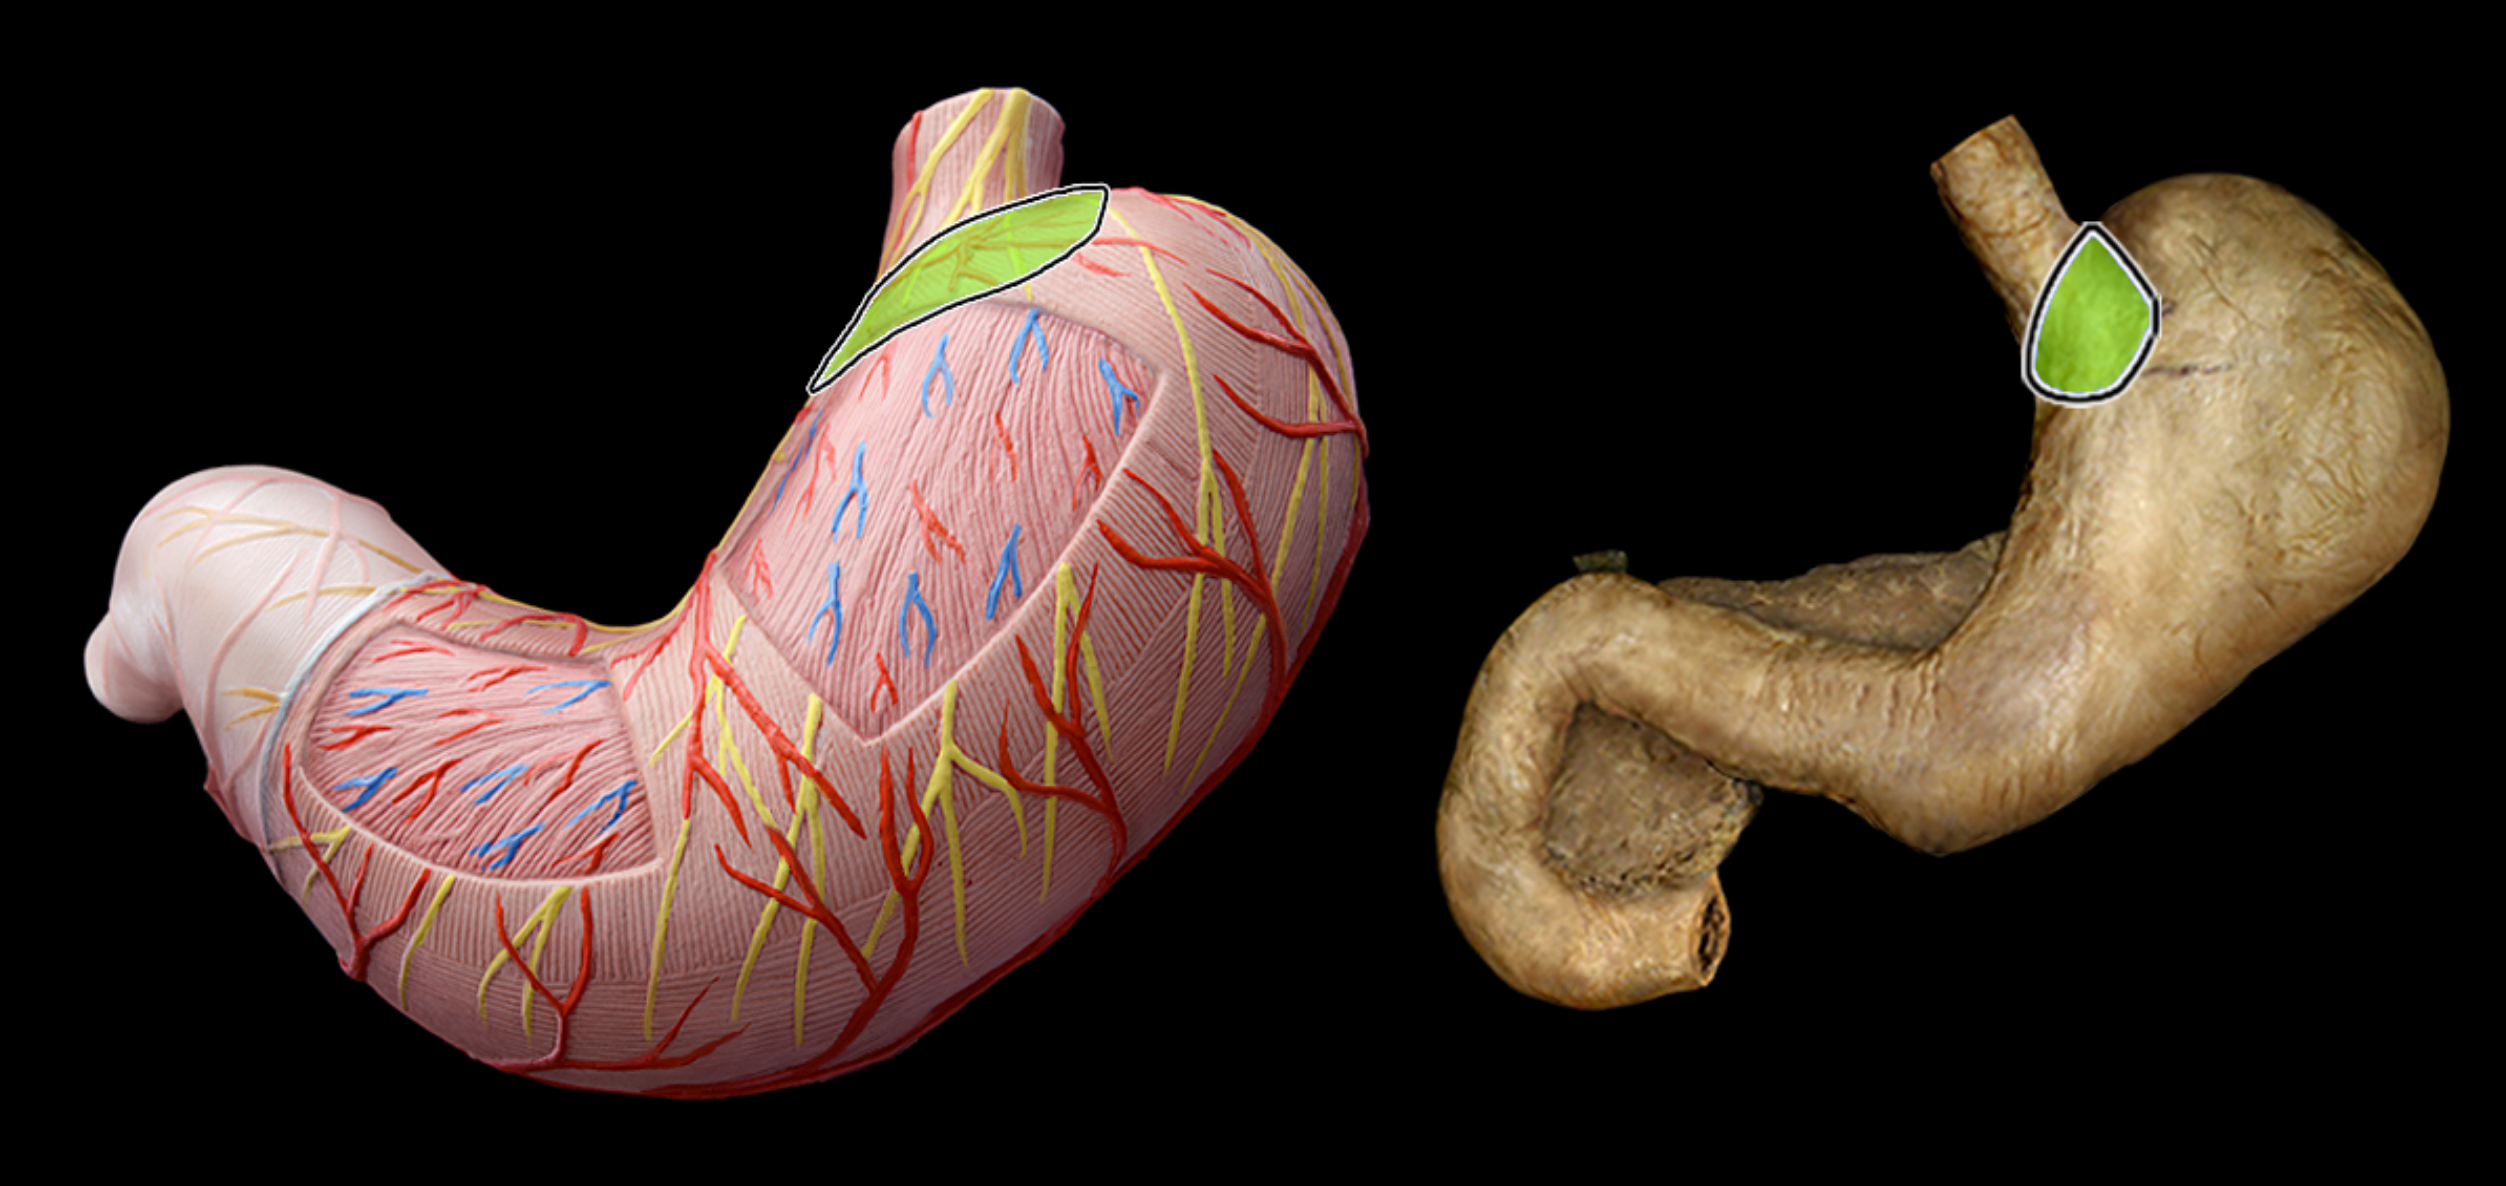

Pyloric part of stomach

Fundus of stomach

cardia of stomach